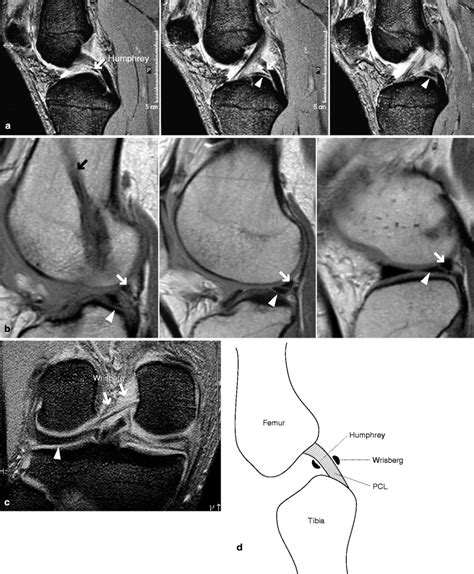

Understand the critical differences between an ACL and PCL tear. Learn the essential symptoms, diagnosis methods, and surgical versus non-surgical recovery options for these common knee ligament injuries. Whether you are dealing with joint instability or seeking effective rehabilitation strategies, our comprehensive guide provides the expert insights you need to restore knee function and return to activity safely.